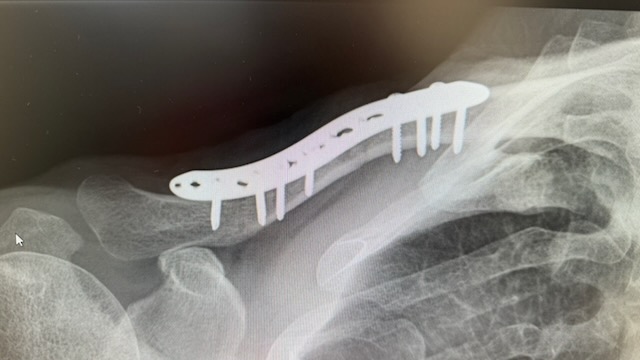

Had a bit of a bad landing a little while back and did my collarbone (and made a mess of my face). I persuaded the docs to plate it and it was finally done 3 weeks after the crash (2 weeks back from today).

My first plate was similar kind of size to yours, maybe a little shorter.

Unfortunately the bone broke at the less protected end instead, so now I have a longer plate.